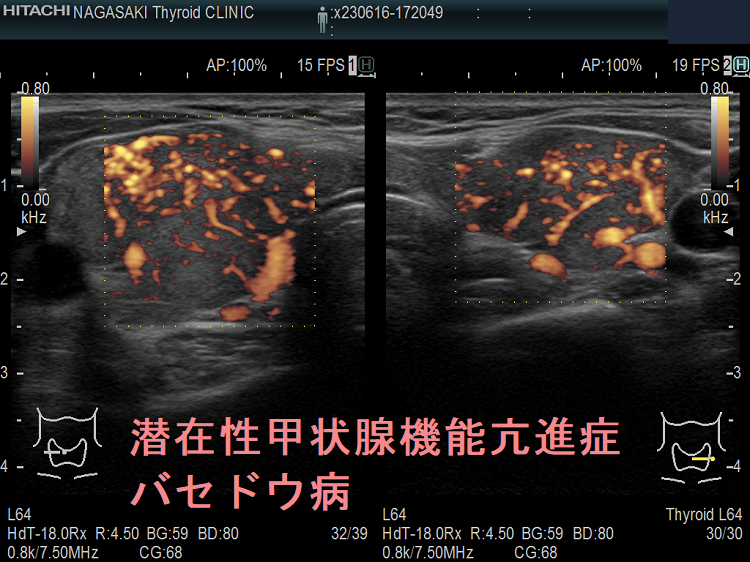

血液検査に加えて、医師は身体検査を行って、甲状腺の肥大や手の震えなど、甲状腺機能不全の兆候がないかどうかを確認します。また、甲状腺の構造を評価するために、甲状腺超音波検査などの画像検査を依頼することもあります。

原因がバセドウ病または中毒性多結節性甲状腺腫である場合、治療の成功率は高く、良好な結果が得られます。ただし、他の病気と同様、見通しは個人と治療に対する反応によって異なります。